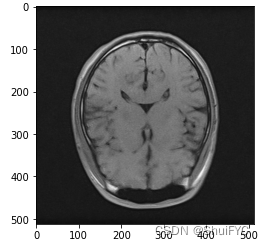

1.1 绘制初始图像

image = sitk.ReadImage('xxx.nii') # <class 'SimpleITK.SimpleITK.Image'> 支持dcm\nrrd\nii

image_array = sitk.GetArrayFromImage(image) # z,y,x shape z*512*512

fig, axes = plt.subplots()

axes.imshow(image_array[8,...], cmap='gray')